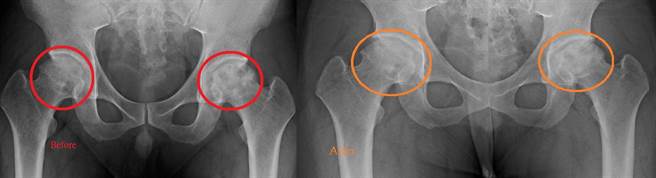

该男在接受2至3次、每次约24000发的骨癒合震波治疗后,经X光检查即可见双侧髋关节均出现明显组织再生与修復,男子亦感觉疼痛感改善很多。杨椒乔提醒,双侧髋关节缺血性坏死患者,越早治疗效果越好。